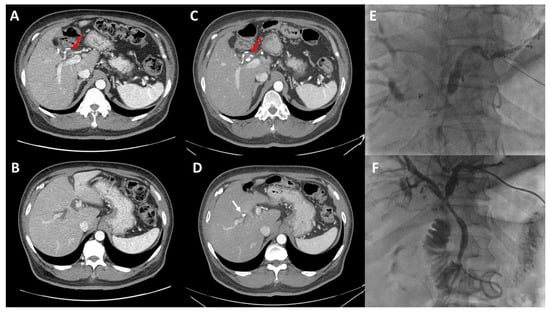

2. Preoperative Imaging